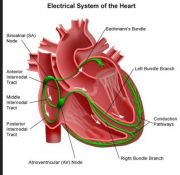

| 2021年7月26日 (一) 20:03 | 心脏电传导系统.jpg (文件) |  |

38 KB | Uploaded with SimpleBatchUpload | 3 |